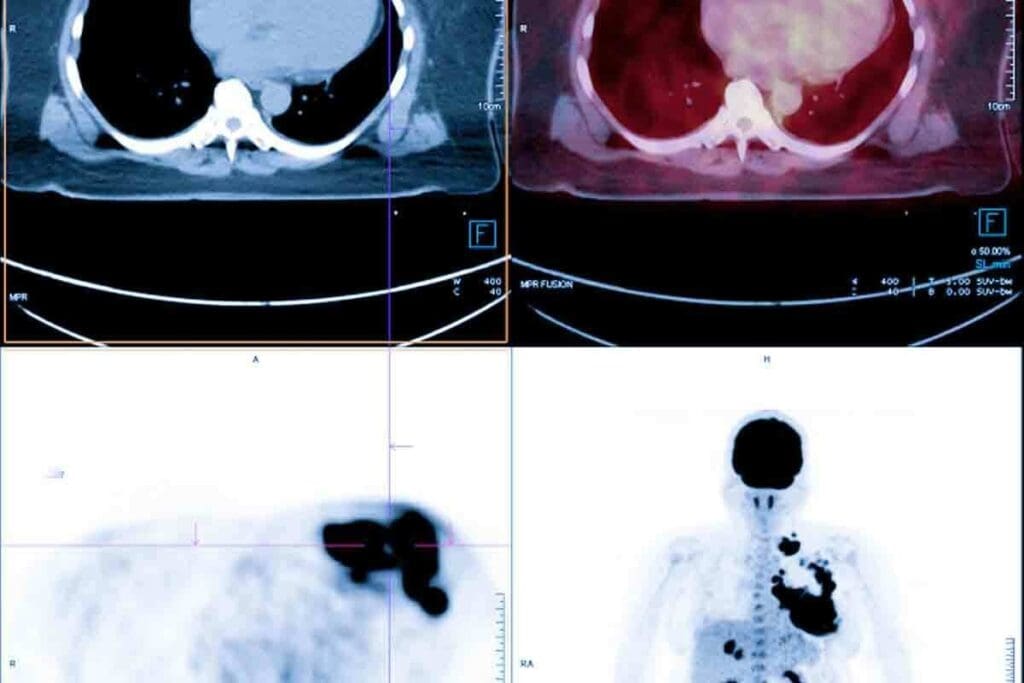

Recent studies have looked into the link between CT scans and cancer. They offer insights into the risks of these diagnostic tools. The worry about CT scans and cancer comes from their growing use and the radiation they expose patients to.

Current Research on CT Scans and Cancer Risk

Many studies have explored the link between CT scans and cancer risk. Research shows that ionizing radiation from CT scans might raise cancer risk, mainly in children and young adults. The risk is higher for those who have multiple CT scans, as more radiation can lead to a greater cancer risk.